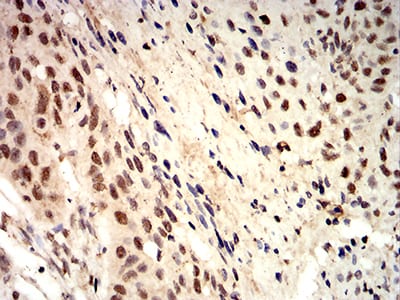

Immunohistochemical analysis of paraffin-embedded human breast cancer tissues using SAPCD2 mouse mAb with DAB staining.

Immunohistochemical analysis of paraffin-embedded human esophageal cancer tissues using SAPCD2 mouse mAb with DAB staining.